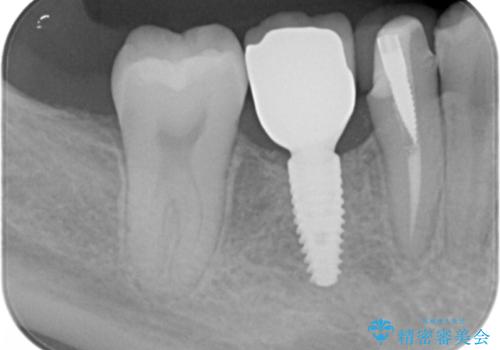

インプラント治療をご希望されたため、植立を行いました。

インプラントを入れる際、部分的に骨を増やす処置を行っています。